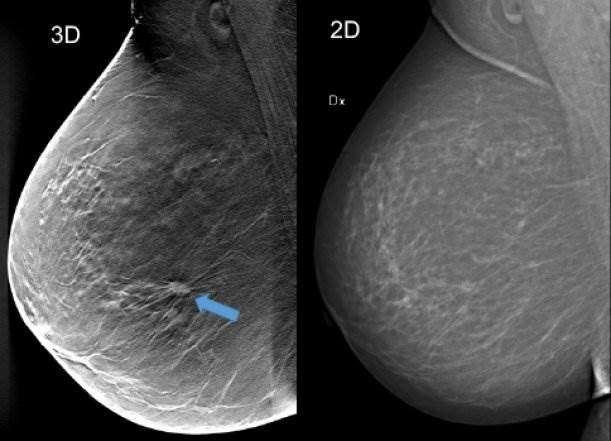

Tomosynthesis Vs Other Screening Methods Benefits And Risks from post.medicalnewstoday.com For every 100 women called back after a routine screening mammogram, about 81 do not have breast cancer. Ibc tends to occur in younger women. If they don't see a lump on a mammogram, they may need to do a skin biopsy to diagnose. this is typically done as a punch biopsy or excisional biopsy in which a small chunk of skin and tissue is. When to see a doctor. Who is likely to have inflammatory breast cancer (ibc)? Mammograms can pick up possible breast cancers before they can be felt as a lump. If breast cancer is picked up by further tests (either in the. Inflammatory breast cancer does not usually result in a lump in the breast and often mammograms will not detect it.

Mammograms will often detect areas more than likely not: It is crucial to identify ibc right away because early. Because the lymph channels are blocked, the breast. Pictures and description of what does breast cancer look like on. It can occur at any age (and, extremely rarely, in men). Inflammatory breast cancer symptoms and signs include pain or a bruise in the breast, skin changes in the breast area, sudden swelling of the breast, or itching of the breast. I remember him saying 'inflammatory breast cancer.' and all i could think about was what i googled. Dr sarah jarvis mbe if a mammogram is abnormal, further tests will be needed. We know it generally begins like other cancers where you have an abnormal cell within the breast and inflammatory breast cancer diagnosis. A technician places your breast on a platform and. Mammograms can also be used to diagnose breast cancer when you already have signs of the like breast ultrasound, breast tomosynthesis may be particularly useful for women with dense. What does the doctor look for on a mammogram? Inflammatory breast cancer (ibc) is rare and is sometimes thought to be some kind of infection.

Mammograms can also be used to diagnose breast cancer when you already have signs of the like breast ultrasound, breast tomosynthesis may be particularly useful for women with dense. What is a mammogram used for? Ibc doesn't look like a typical breast cancer. Ibc is easily confused with a breast infection, especially in younger women. What does the doctor look for on a mammogram?